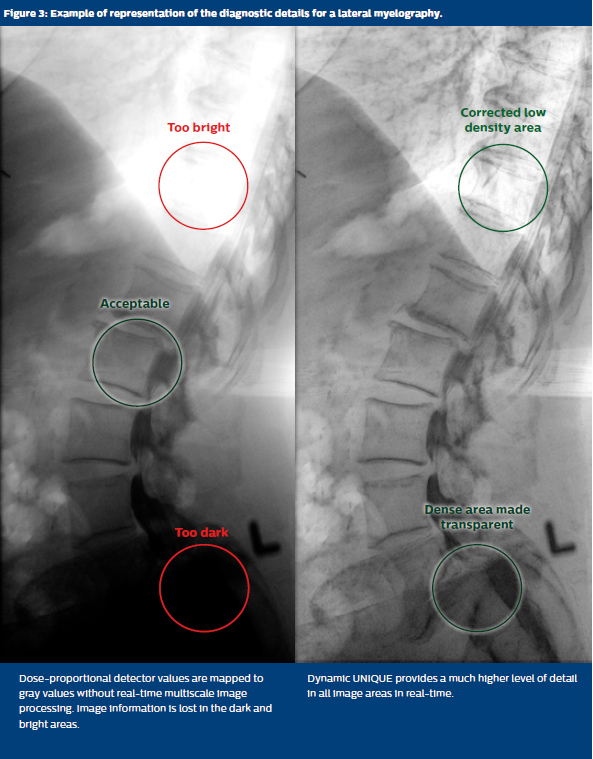

Dynamic UNIQUE is a second-generation multiscale image enhancement that provides a high level of detail, according to the diagnostic need, in real time. Each single frame is fully processed, without significant additional computation time (below 14 ms for fluoroscopy, below 55 ms for exposures), even at high frame rates (up to 30 fps). Therefore, the diagnostically important image content is optimally enhanced according to the clinical task. Dynamic UNIQUE features a perfect harmonization of areas filled with contrast agent, soft tissue, and bones, even in challenging viewing conditions with large variations in tissue radio-density. Contrary to traditional multiscale enhancement algorithms, Dynamic UNIQUE processing strictly separates global and local contrast enhancement, preventing undesired enhancement artifacts. If desired it is easily customizable according to the diagnostic need.

Optimal representation and visibility of diagnostically important information results in an enhancement of diagnostic details, such as small vessels and catheters, without enhancement artifacts or image clipping. A lessened risk to miss important details leads to an increase in diagnostic confidence.